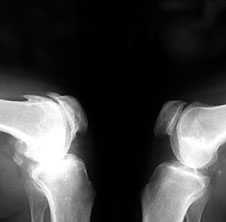

3. Заострение краев суставных поверхностей мыщелков бедренной и большеберцовой кости, чаще в медиальном отделе сустава (связано с большей нагрузкой на этот отдел сустава), особенно при наличии варусной деформации сустава; реже - в латеральной части или одновременно в обеих половинах суставной поверхности (рис. 2).

Рис. 2. Rо-графия коленных суставов в боковой проекции.

Артроз феморопателлярных суставов (больше слева). Артроз коленных суставов (I ст по Kollgren справа, IV ст. по Kollgren слева)